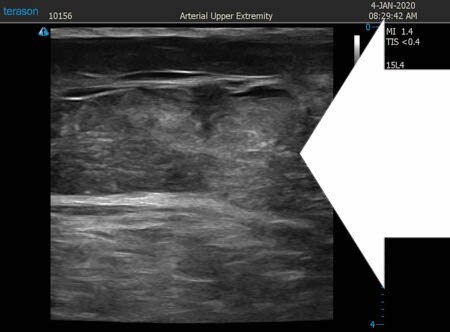

いつものように3Dタッチビュー(超音波)で

皮下脂肪層を評価してみましょう。

左太もも前面。

同様に右太もも前面。 ↓ ↓ ↓

右太もも後面。

左太もも後面。